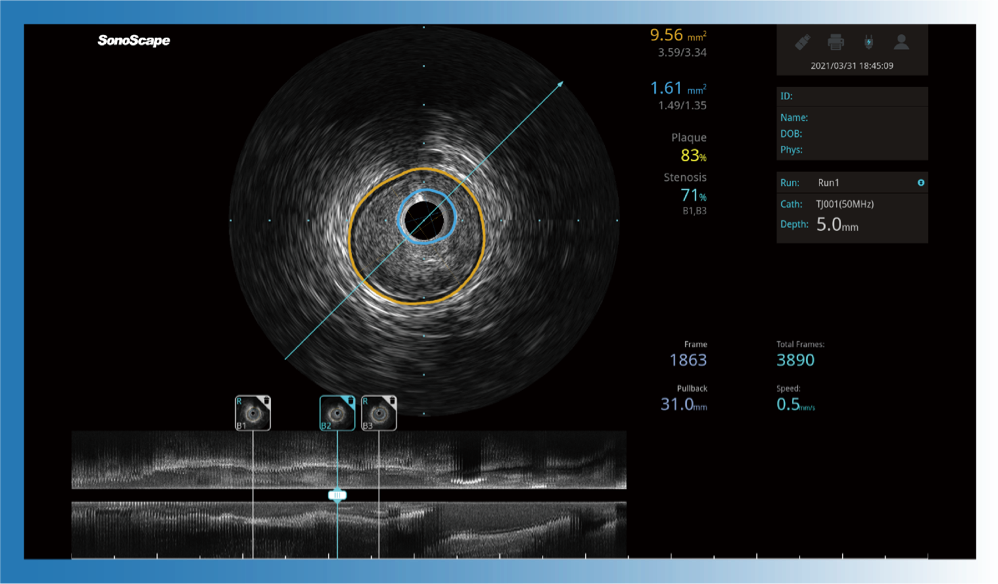

对比传统IVUS导管成像,环球UG官网宽频IVUS图像的近场支架梁显影更细腻,远场中膜外血管仍清晰可辨,兼顾远中近,兼顾分辨力与穿透深度

一键智能描迹,自动测量斑块负荷、面积狭窄率等指标,准确率高于90%